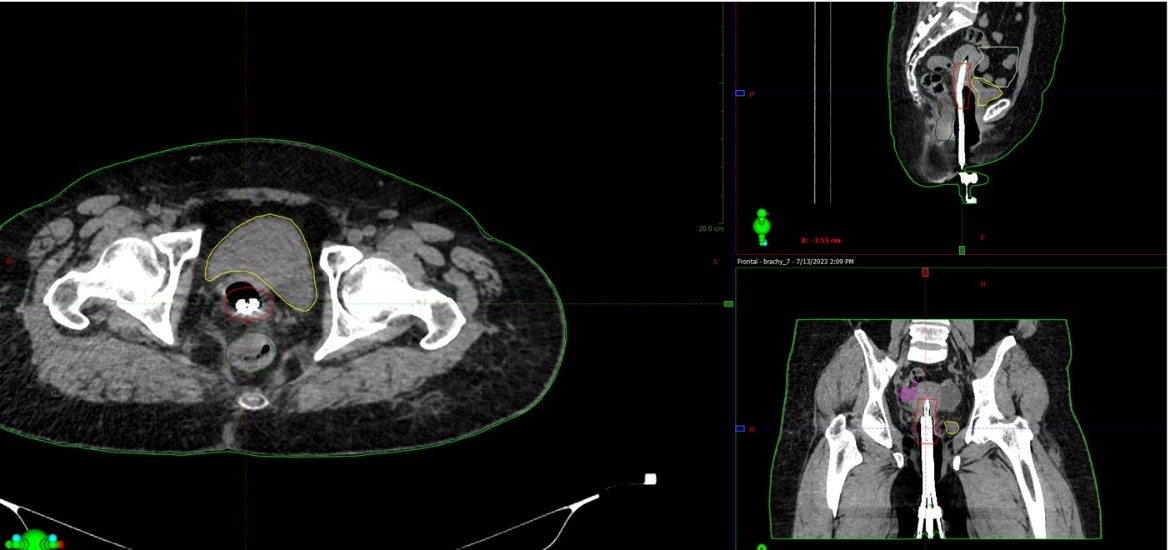

Qaterli isikti emdeýdiń taǵy bir tıimdi ádisi – sáýleli terapııa. Bıylǵy mamyr aıynan bastap batysqazaqstandyqtardyń da bul emge qoly jetti. О́ńirde ıadrolyq medısına ortalyǵy ashylǵanyn budan buryn súıinshilep jazǵan edik. Sodan beri ótken az ýaqyt ishinde oraldyq mamandar radıologııanyń sońǵy múmkindikterin paıdalanyp, qaterli isikti sáýlemen emdeýdiń sý jańa eki tásilin engizip úlgergen. Onyń birinshisi – jatyr moıny qaterli isigin sáýlemen emdeýde 3D josparlaý kómegin paıdalaný. Bul degenińiz – brahıterapııanyń ár satysynda kompıýterlik tomografııa kómegimen 3D kórinis arqyly em júrgizý degen sóz. Qazaqstan boıynsha mundaı em tek 2D kórinis arqyly júrgiziledi. Oraldyqtar jańa ádis úshin arnaıy baǵdarlama jasap, kompıýterlik tomografııa, ýltradybystyq jáne magnıtti-rezonansty tomografııa zertteýleriniń bir-birimen úılesýin qamtamasyz etti, mamandardy oqytyp úıretti.

Qaterli isikti 3D josparlaý tásilimen emdegen kezde sáýle kózdegen núktege óte dál túsedi, sol arqyly emniń paıdaly áseri kóbeıip, nátıje artady jáne jalpy emdeý merzimi qysqarady. Em sońynan bolatyn asqyný azaıyp, tik ishek, qýyq sekildi mańyzdy aǵzalar zaqymdanbaıdy.

– Árıne, 3D brahıterapııa ádisi bizdiń jumysymyzdy kúrdelilendire tústi. Biraq jatyr moıny qaterli isigi dıagnozymen kelgen naýqastar úshin biz esh qıyndyqtan qashpaımyz. Qazir bul emdi onkogınekolog-radıolog dáriger B.Qojas pen medısına fızıgi D.Ýálsherov júrgizip jatyr, – deıdi Iаdrolyq medısına ortalyǵynyń jetekshisi Aleksandr Kýznesov.